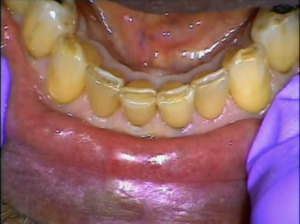

Deep, Discoloured Grooves on Your Lower Front Teeth — Class 6 Incisal Wear

Class 6 incisal wear describes the deep, discoloured grooves that develop along the biting edges of lower front teeth. What begins as surface discolouration becomes a hollow trough through the enamel and into the dentine beneath, leaving a thin, fragile enamel rim that is increasingly prone to decay and fracture.

- To restore the biting edge. Advanced wear flattens and weakens the incisal edge, reducing chewing efficiency and altering the bite. A filling restores the tooth’s original form and function.